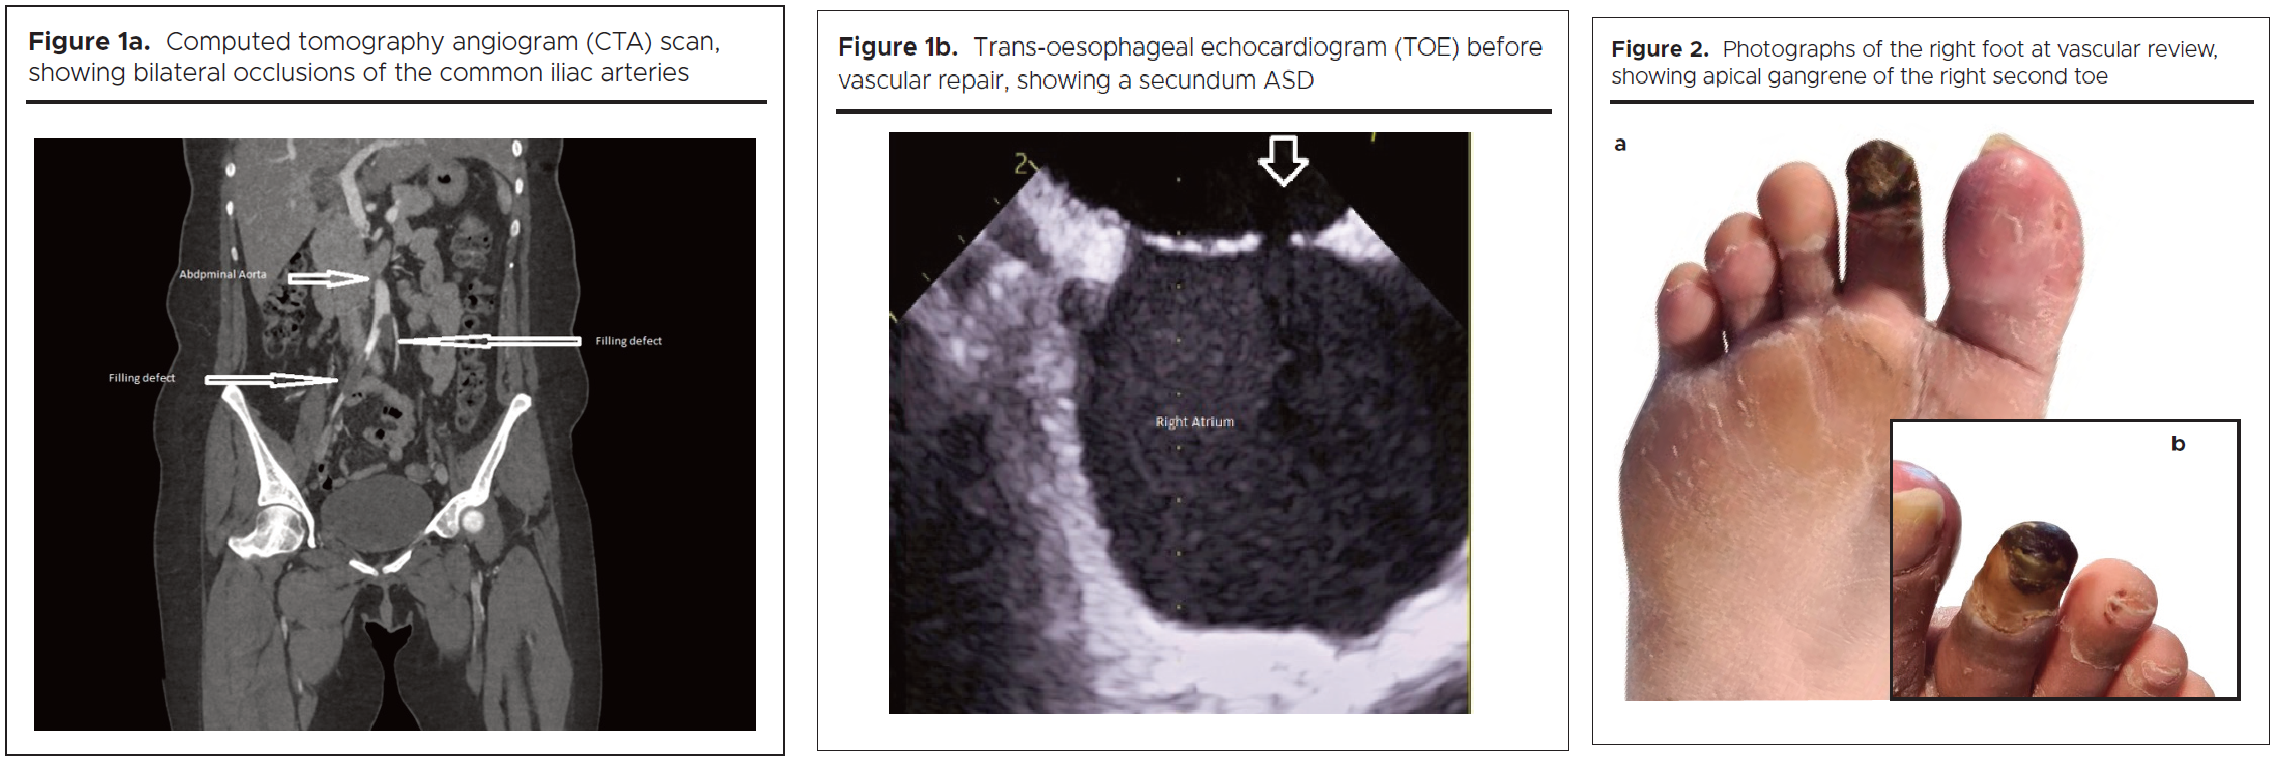

Therapeutic intervention

With limb-threatening ischaemia identified, bilateral iliac embolectomy and a kissing common aorto-iliac revascularisation procedure took place. Following recovery from this, in July 2024, she underwent successful ASD AmplatzerTM device closure (figures 3a and b).

1455-figures-3a-2b

A TOE showing a pulmonary-to-systemic flow ratio (Qp/Qs) of 1.6:1 is indicative of a significant left-to-right shunt. Along with paradoxical embolism, it was an indication for closure of the atrial communication in our patient.